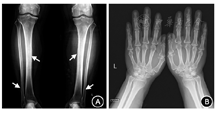

因患者清晨空腹随机GH正常,服糖后GH可被抑制至1 μg/L以下,且存在低钾血症,进一步进行除外肥大性骨关节病(HOA)的检查:胫腓骨正侧位(双侧)提示双侧胫腓骨皮质稍增厚,双侧膝关节骨质增生;双手放大X线片示双手多发近节指骨骨膜反应可能,双腕头状骨多发囊变(图3);停用寿比山后血钾恢复正常;甲状旁腺素(PTH)、游离钙、降钙素、24 h尿电解质、血尿蛋白电泳、抗核抗体谱、癌胚抗原等肿瘤指标均未见异常,胸部和肾上腺CT未见占位。结合患者临床表现和检查结果,考虑不除外轻型垂体GH腺瘤可能。经过多科讨论,2017年8月4日患者在全麻下行神经内镜经鼻蝶窦入路垂体探查及鞍底重建术。术中见肿瘤主要位于鞍内靠下靠后,质地软,为灰白色,血运不丰富,大小约7 mm×6 mm×5 mm,术后第2天清晨空腹随机GH降至0.8 μg/L,IGF-1降至142 μg/L,较术前明显下降。葡萄糖GH抑制试验:GH基础值为0.8 μg/L,谷值为0.4 μg/L。病理回报:垂体腺瘤。免疫组化结果:GH(+),黄体生成素(LH)(-),卵泡刺激素(FSH)(+),ACTH(-),催乳素(-),促甲状腺激素(-),P53(-),Ki-67指数:4%(图4)。

注:A.患者胫腓骨正侧位(双侧):双侧胫腓骨皮质稍增厚,双侧膝关节骨质增生(↑);B.患者双手放大相:双手软组织增厚,多发近节指骨可见骨膜反应,双腕头状骨多发囊变区